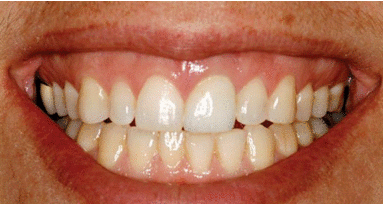

Bien que ce traitement ait été développé avec considération de l'occlusion du patient, des circonstances mécaniques et des habitudes, à la suite de la fracture des implants, une analyse rétrospective de l'emplacement prévu pour les implants a révélé un deep-bite sur les modèles en articulateur et une usure occlusale généralisée de la denture opposée (Fig. 2).